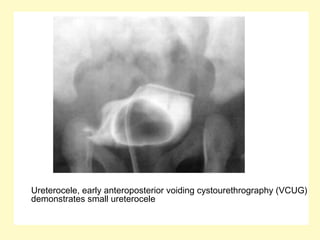

Ureterocele, early anteroposterior voiding cystourethrography (VCUG)

demonstrates small ureterocele

Ureterocele, early anteroposteriorvoiding cystourethrography (VCUG) demonstrates small ureterocele